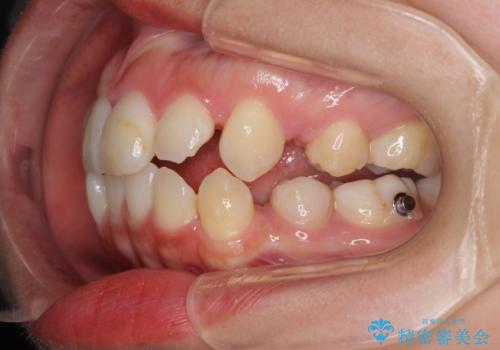

- 口元の突出感を気にして来院された患者様です。

診断の結果、上顎左右第一小臼歯4本抜歯により、叢生を解消するとともに口元を引っ込めていくことが望ましいと判断しました。

抜歯矯正による口元の改善にはワイヤー矯正が望ましいのですが、ダンサーとしての仕事を行っているため、インビザラインにて治療を行うこととしました。